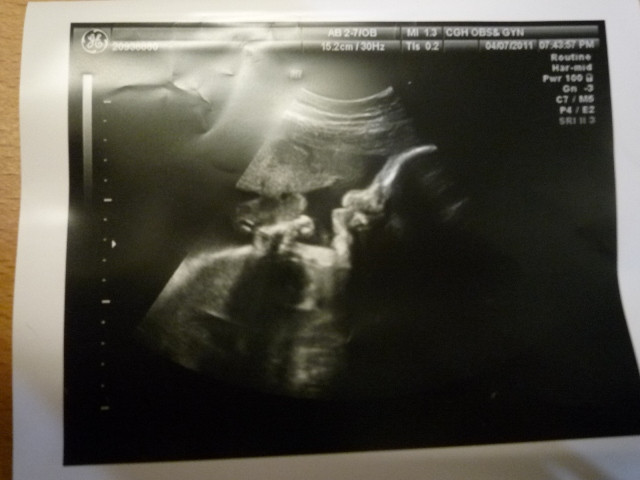

<!-- Origin Article URL: http://www.wretch.cc/blog/sammieu/27680630 --> <img src="https://pimg.1px.tw/sammieu/1378694461-655868618.jpg"> <br>小豆子31週大了!<img src="http://l.yimg.com/e/serv/blog/smiley/msn/y19.gif"><br>目前預估重量1881g,我覺得可能是因為頭大,所以體重超標,實際上應該沒那麼重。<br><br>這是側面照,都起來那個不知是鼻子或嘴吧‧‧‧‧‧‧<br>往上舉的不知是手或腳‧‧‧‧‧‧<br>總之他是好動的寶寶,常常翻滾,踢來踢去‧‧‧‧‧‧<br><br>小豆子繼續長大唷!<br>還是當個雙子寶寶吧!